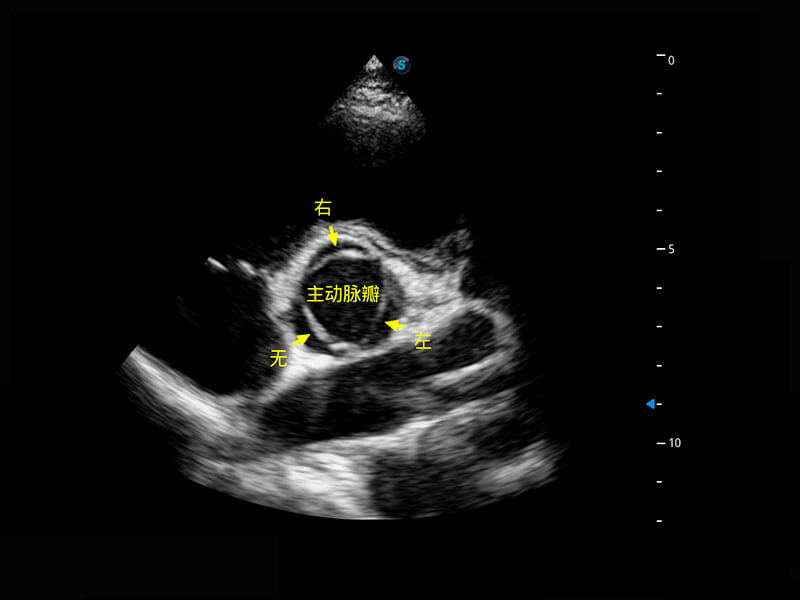

P60搭载一系列胎儿心脏成像技术,实现精细的胎儿心脏评估。

• 四腔切面

• 四腔心血流

• 右室双出口

• 胎心容积成像